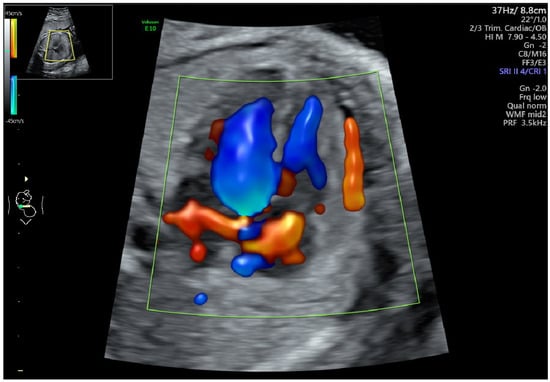

2.1. Defining of Functional Abnormalities